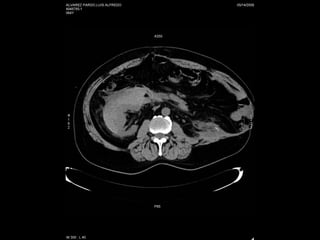

TOMOGRAFIA COMPUTADA Excelente caracterización anatómica. Ampliamente disponible Relativamente sencilla de interpretar. Detecta todos los cálculos* Irradia Reacciones adversas al medio de contraste

TC

UROTC